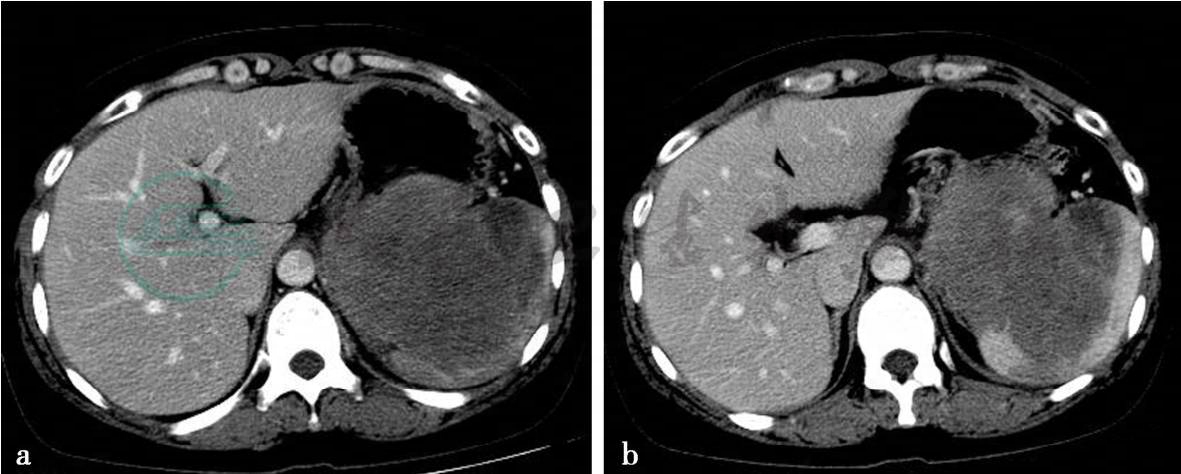

图3 图3a~c,轴位增强静脉期图像。左上腹低密度肿块,累及脾脏、胰尾及胃底。增强后呈轻度不均匀强化